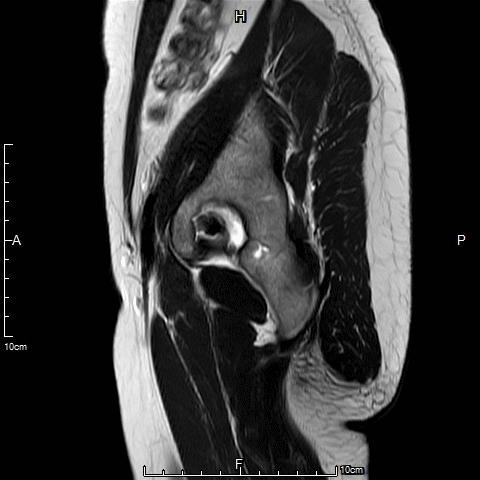

- 术前MRI显示子宫明显增大,病灶主要位于子宫前壁。

- 术后3个月复查MRI显示子宫明显缩小,前壁病灶萎缩坏死。

- 术前MRI检查显示子宫明显增大,弥漫型子宫腺肌症。

- 术后复查MRI显示子宫明显缩小,腺肌瘤明显坏死吸收。

中年女性,痛经10余年,近3个月明显加重。痛经达重度疼痛,严重影响生活质量。磁共振检查显示子宫前壁囊性病灶。临床诊断为囊性子宫腺肌症。